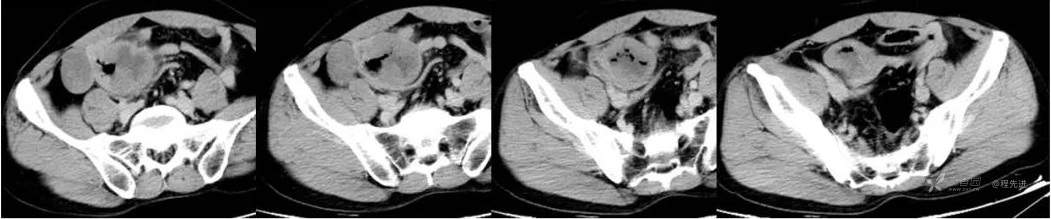

延迟期